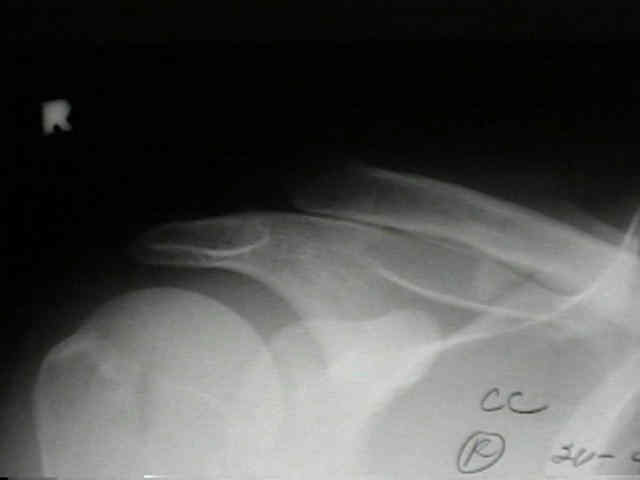

AC Joint 1 AC Joint 2 AC Joint 3 AC Joint 4

• 20-year-old who fell on tip of right shoulder, but did not show radiographic signs of AC joint injury in the ER;

• one month later the patient continued to have pain, and radiographs demonstrated greater than 100 percent displacement of AC joint on both AP and Cross Body AP (Cross Adduction View);